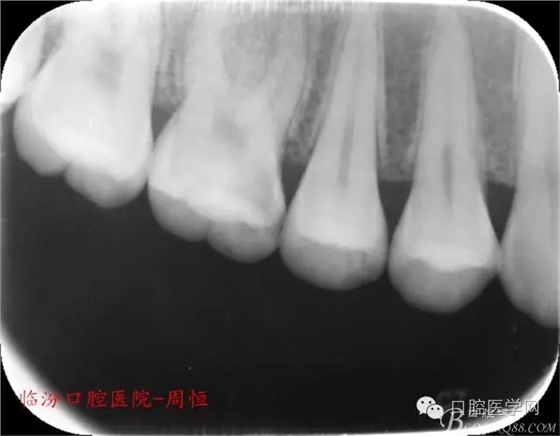

X 示:近中低密度陰影達髓腔,牙根未見異常。

圖1 X示 術(shù)前